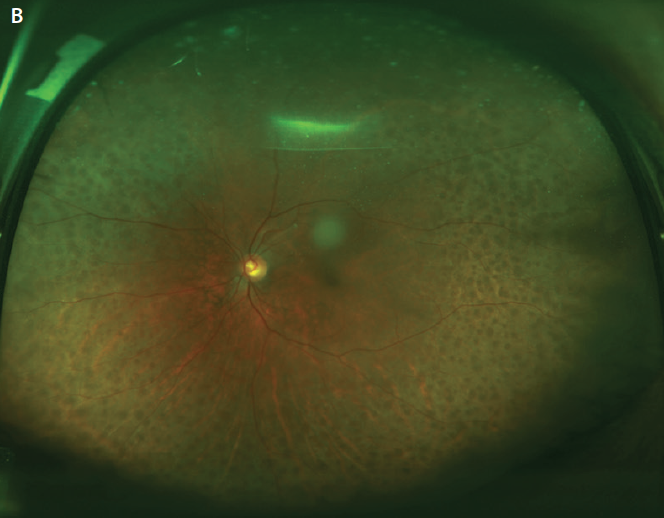

The disease course is typically relapsing and remitting. Gradual superior visual field loss is the most common initial complaint, but patients may also report blurred vision or metamorphopsia.2 The magnitude of choroidal elevation in UES is highly variable, but it typically begins in the periphery. Simultaneous exudative retinal detachment that can involve the macula may occur (Figure 1A). Deep retinal or subretinal exudates may appear prior to serous detachment, and optic nerve edema may be present.2,3 There may be mild to moderate vitreous cell.2 Hyperpigmented changes in the retinal pigment epithelium (RPE), termed leopard spots, and permanently reduced VA can occur with chronic disease (Figure 1B).4 Spontaneous resolution occurs in most cases but may take months or several years.2

Figure 1. Widefield color fundus photograph of an eye with UES depicting peripheral choroidal effusions with overlying serous retinal detachment (A). Postoperative appearance of the same eye after the creation of scleral windows shows flattening of the choroidal effusions and resolution of the serous retinal detachment with VA of 20/30. Persistent leopard spot hyperpigmentation is seen (B).